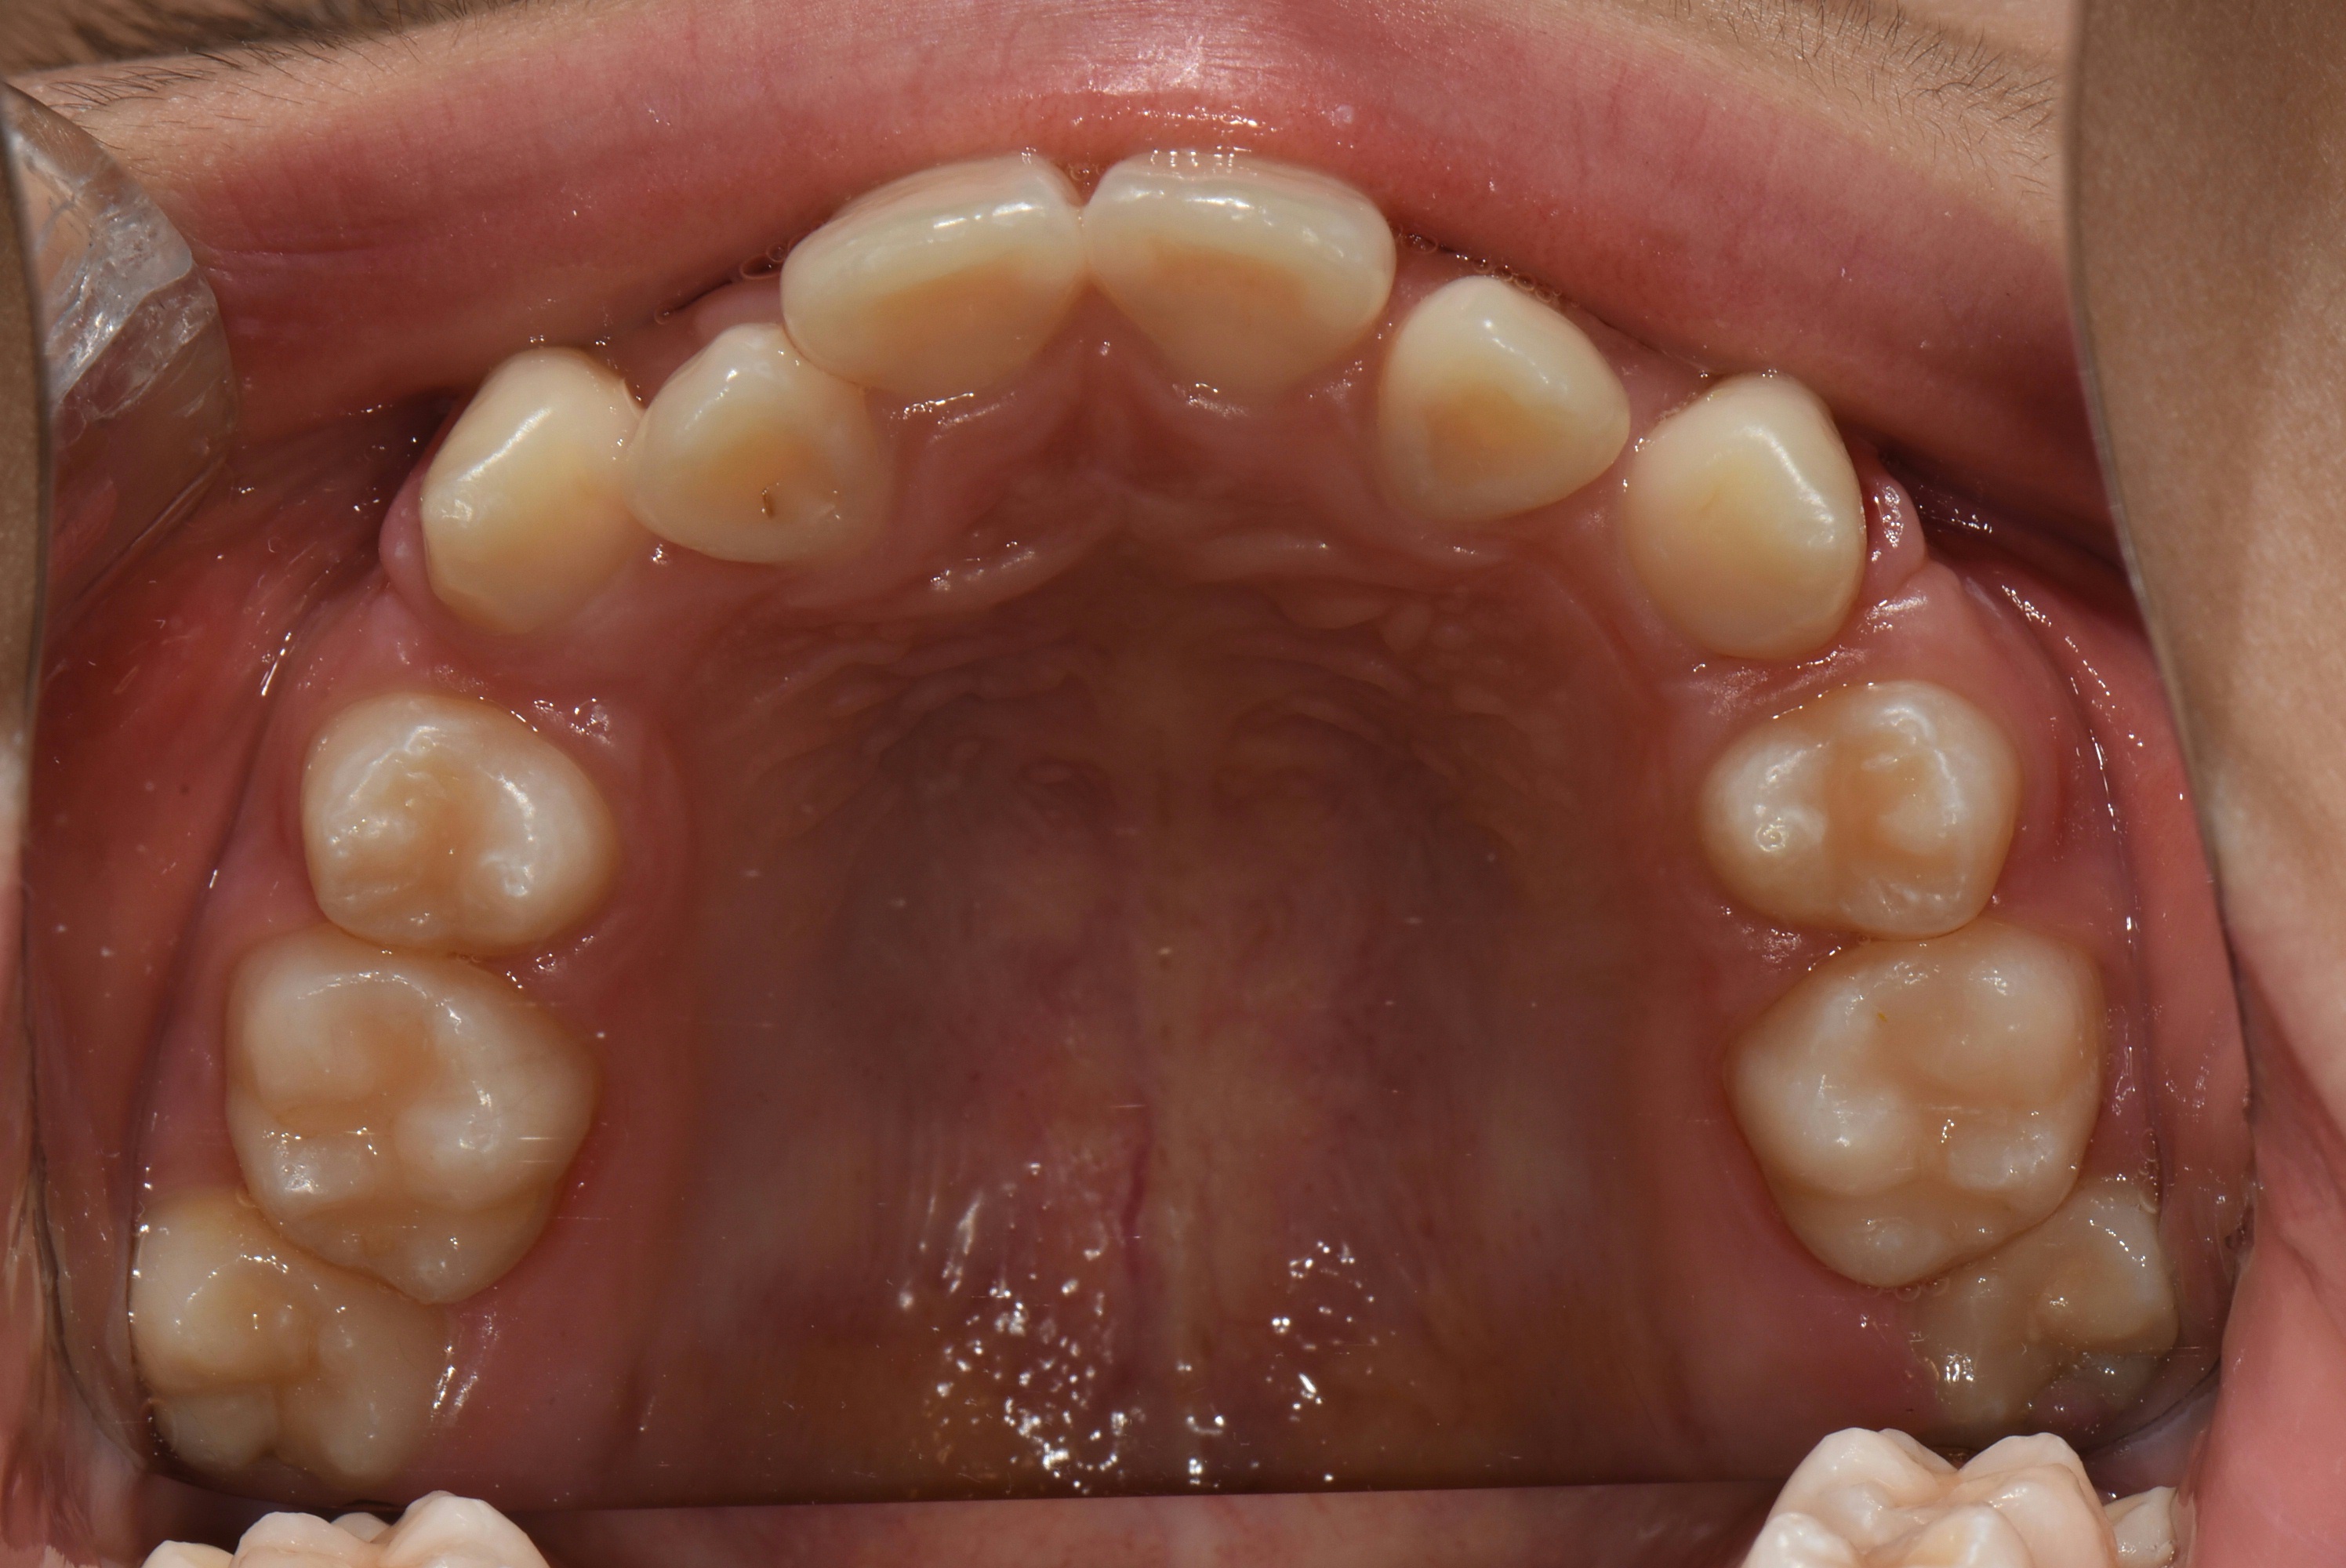

치료 전 사진입니다.